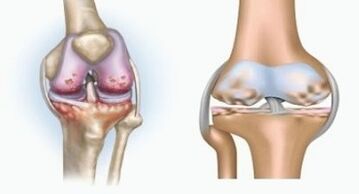

Both pathologies affect the joints, but differ in the nature of changes.

With arthritis

Arthritis is an inflammation of connective tissue - a synovial membrane that contains many vessels and provides lymphatic flow.The inflammatory process leads to a violation of the nutrition of joint tissues, as a result of which joint lubrication production - synovial fluid is limited.

With arthrosis

Arthrosis is a degenerative degenerative process associated with the destruction of the articulation cartilage tissue.The cartilage is gradually destroyed, dry, the distance between the bones of the joint decreases, which is the cause of pain.In serious forms, destruction affects bones.They become more porous, lose their density, become fragile.